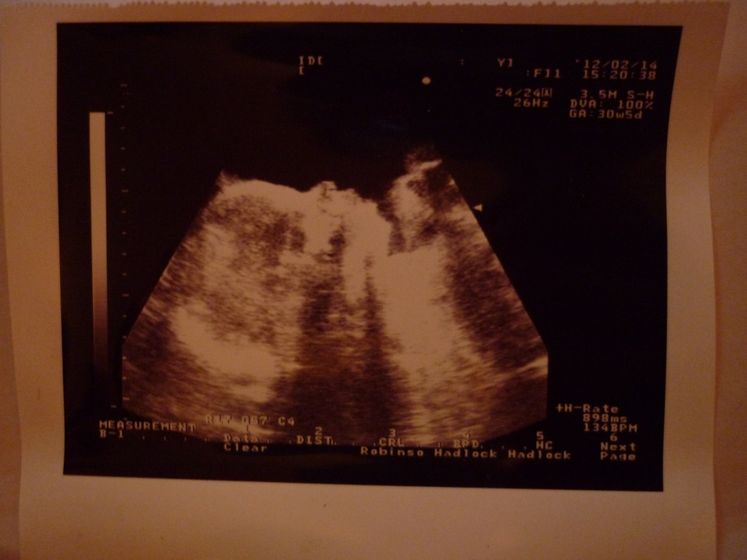

опустился.....36